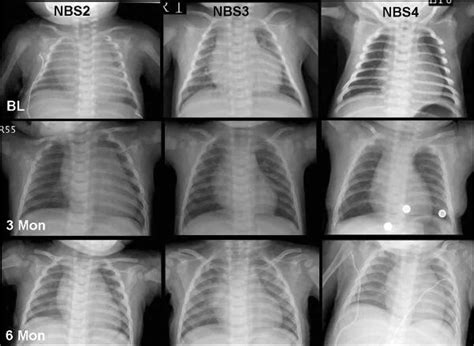

Infantile-onset Pompe disease is the most severe form, typically presenting within the first few months of life. Because the deficiency of the GAA enzyme is usually profound, the accumulation of glycogen happens quickly, primarily affecting the heart and skeletal muscles.

• Respiratory distress: Frequent lung infections and difficulty breathing.